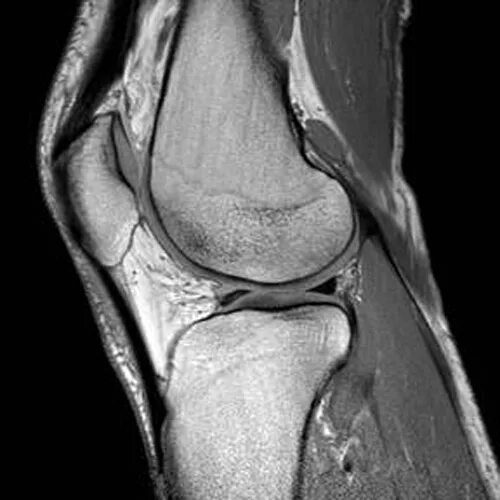

Мрт коленного сустава одежда